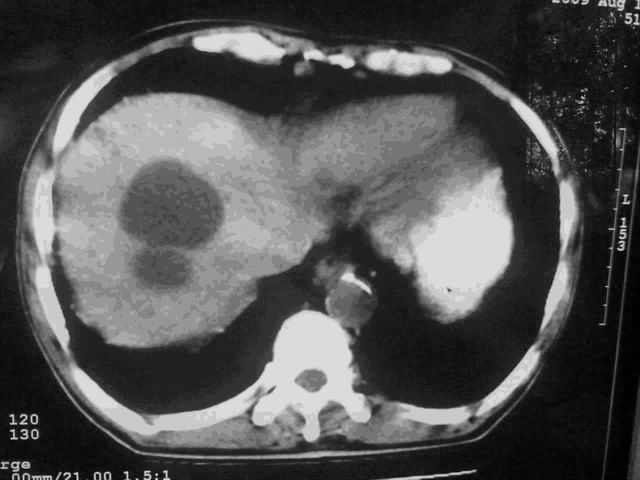

我这个考考大家眼力,看看是升结肠ca还是降结肠ca

好象是横结肠占位肝转移,胰头占位?【伙计,您的片也真够意思】

横结肠占位肝转移

伪影太多,考虑降结肠癌伴肝转移,胆囊炎

伪影太多,考虑升结肠癌伴肝转移,胆囊炎

好象是横结肠占位肝转移,胰头占位?

考虑升结肠癌伴肝转移;胆囊炎。

好象是横结肠占位肝转移.

结肠占位并肝及腹膜后淋巴结转移。

明确考眼力!考虑降结肠癌伴肝转移可能性。

考虑升结肠癌伴肝转移;胆囊炎

伪影太多,考虑降结肠癌伴肝转移,胆囊炎。